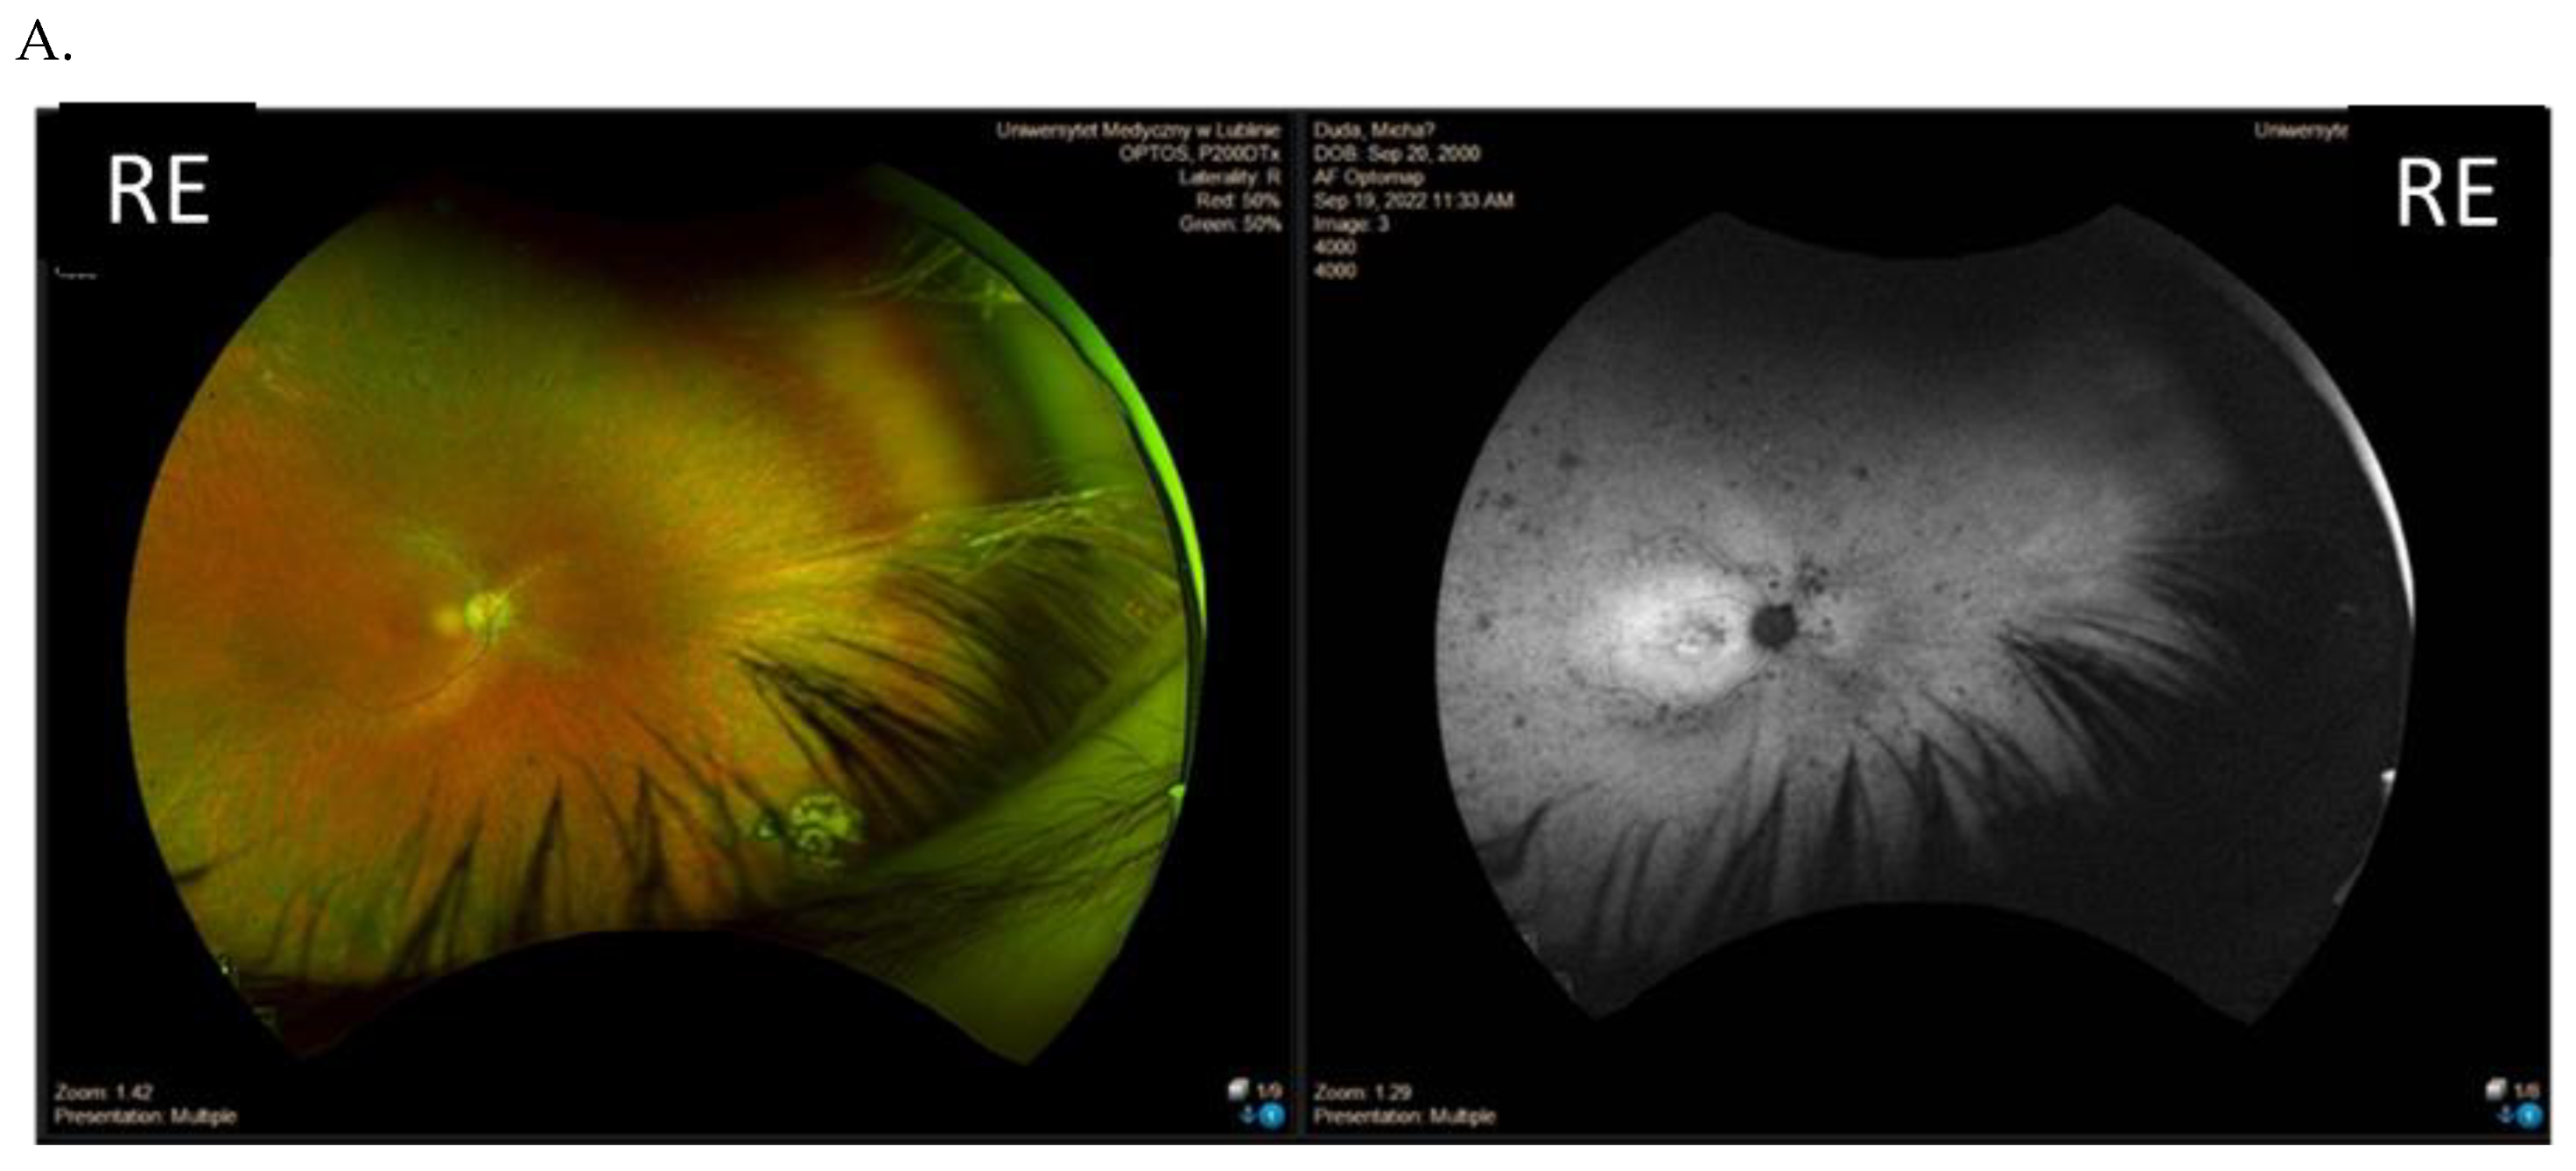

| I (family 1) | c.2442_2445del | 10 | 31 | 0.7 0.7 | Advanced constriction, only V4e remarkable | 277 264 |

| II (family 2) | c.2340_2341del | 12 | 42 | 0.01 0.01 | Advanced constriction, only V4e remarkable | 208 205 |

| III (family 3) | c.2587G>T | 8 | 36 | 0.5 0.6 | Middle constriction, V4e, III4e and I4e remarkable | 143 147 |

| IV (family 4) | c.2389dup | 10 | 22 | 0.7 0.7 | Middle constriction, V4e, III4e remarkable | 223 225 |

| V (family 4) | c.2389dup | 10 | 22 | 0.4 0.2 | Middle constriction, V4e, III4e and I4e remarkable | 260 240 |

| VI (family 5) | c.2455dup | 14 | 25 | 0.6 0.3 | Middle constriction, V4e, remarkable | 205 186 |

| VII (family 6) | c.593G>T | 12 | 20 | 0.5 0.5 | Middle con-striction, V4e, III4e and I4e remarkable | 250 245 |

| VIII (family 7) | c.799G>C | 6 | 47 | 0.2 0.3 | Middle con-striction, V4e, III4e and I4e remarkable | 240 230 |